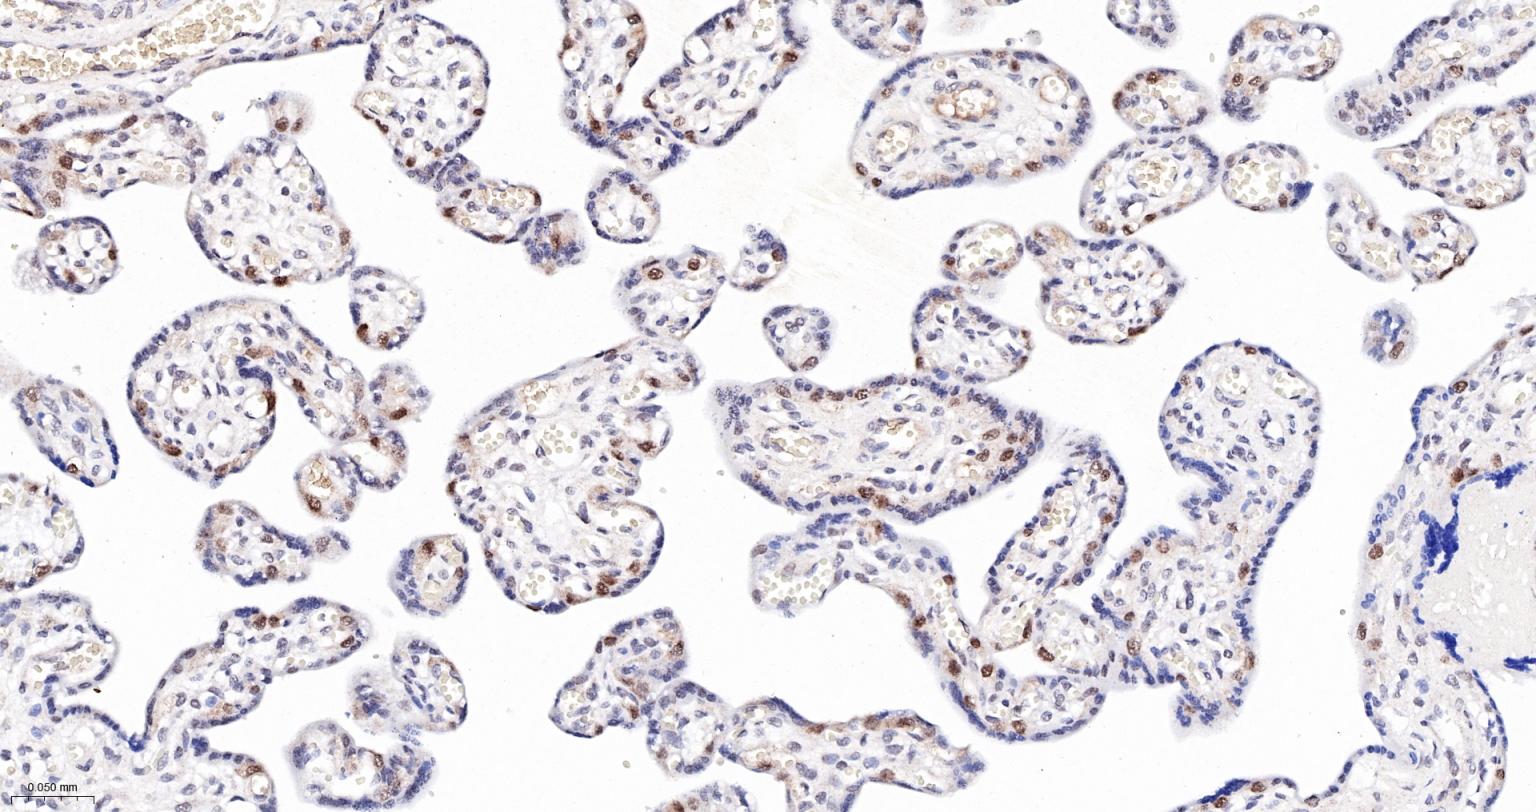

Paraformaldehyde-fixed, paraffin embedded Human Placenta; Antigen retrieval by boiling in sodium citrate buffer (pH6.0) for 15 min; The section was incubated with MAD2L1BP Monoclonal Antibody, Unconjugated (bsm-61271R) at 1:200 overnight at 4°C, followed by conjugation to the bs-0295G-HRP and DAB (C-0010) staining.